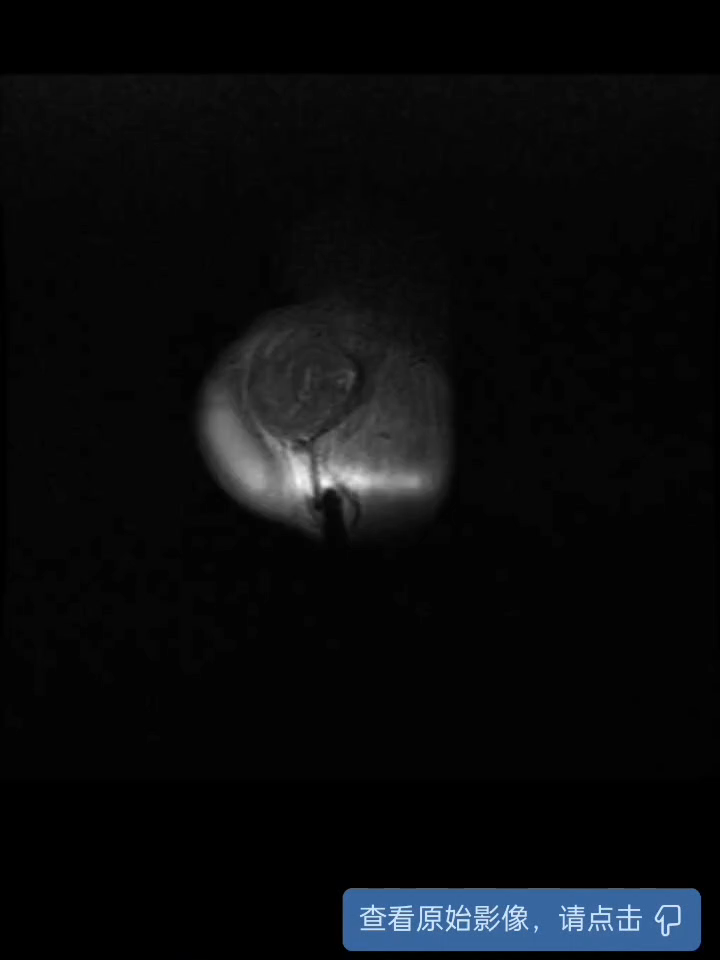

【治疗经过及结果】:完善睾丸及附睾彩超提示左侧睾丸、左侧附睾增大,左侧睾丸、左侧附睾实质回声不均质,考虑睾丸附睾炎可能,但不排除睾丸肿瘤可能,予进一步完善下腹部MRI了解病情;针对患者情况,予选用广谱抗生素,故予抗感染,止痛治疗。

磁共振结果:

但5年前患者隐睾扭转时,曾建议行左侧睾丸切除术,患者家属拒绝,术后也交代术后癌变可能,现在看来,还真有可能术后出现了癌变。成年人的隐睾和小孩子的隐睾还是不一样的,一般如果有孩子的话,反而保留不见得一定有益。